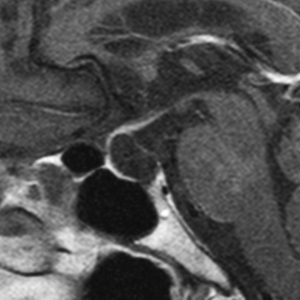

鞍上部クモ膜のう胞

20歳代の女性の無症候性のものです。水色に塗ったのがクモ膜のう胞です。特徴的なのは,下垂体柄が長〜く伸びて細くなっていることです,でも下垂体障害はでません。珍しいことですが,松果体のう胞(黄色の部分)が合併しています。治療の必要がないものです。